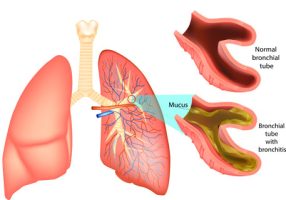

Bronchitis